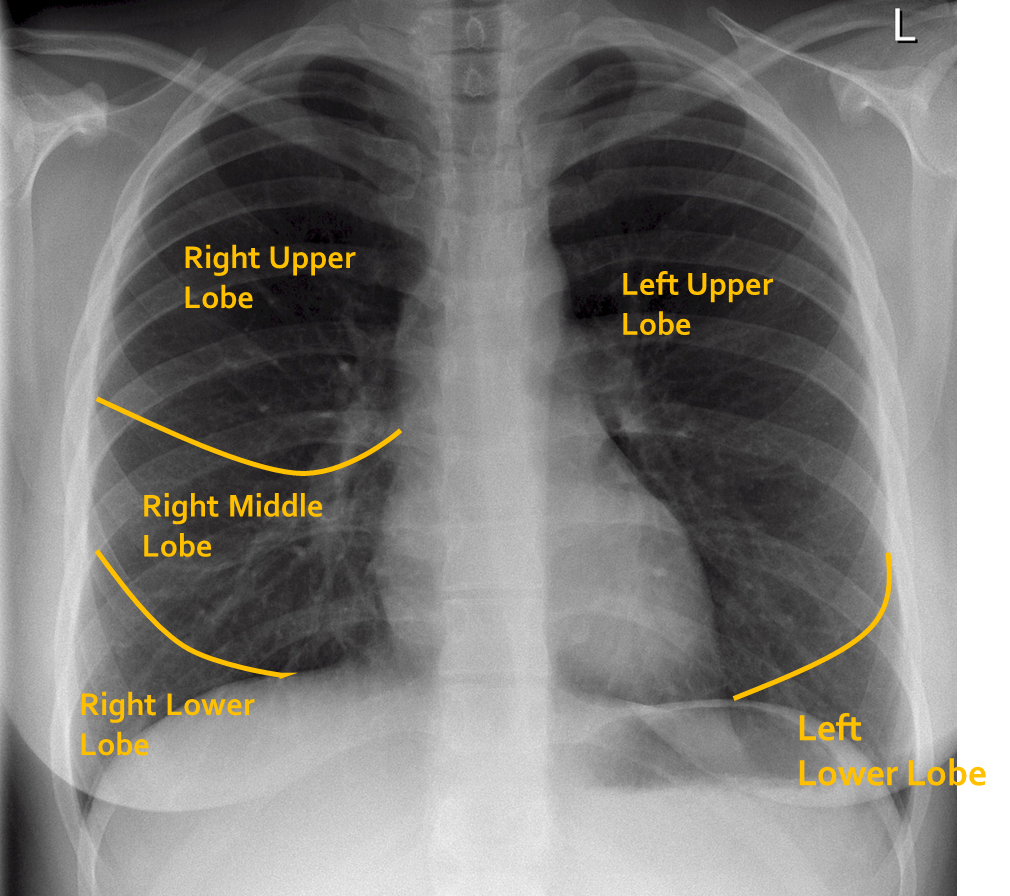

How many lobes are there on each lung